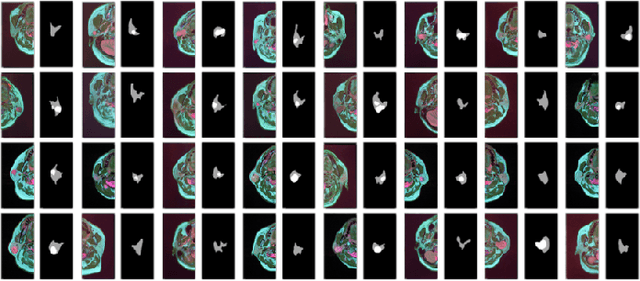

Abstract:Compared with natural images, medical images are difficult to acquire and costly to label. Contrastive learning, as an unsupervised learning method, can more effectively utilize unlabeled medical images. In this paper, we used a Transformer-based contrastive learning method and innovatively trained the contrastive learning network with transfer learning. Then, the output model was transferred to the downstream parotid segmentation task, which improved the performance of the parotid segmentation model on the test set. The improved DSC was 89.60%, MPA was 99.36%, MIoU was 85.11%, and HD was 2.98. All four metrics showed significant improvement compared to the results of using a supervised learning model as a pre-trained model for the parotid segmentation network. In addition, we found that the improvement of the segmentation network by the contrastive learning model was mainly in the encoder part, so this paper also tried to build a contrastive learning network for the decoder part and discussed the problems encountered in the process of building.

Abstract:Parotid gland tumors account for approximately 2% to 10% of head and neck tumors. Preoperative tumor localization, differential diagnosis, and subsequent selection of appropriate treatment for parotid gland tumors is critical. However, the relative rarity of these tumors and the highly dispersed tissue types have left an unmet need for a subtle differential diagnosis of such neoplastic lesions based on preoperative radiomics. Recently, deep learning methods have developed rapidly, especially Transformer beats the traditional convolutional neural network in computer vision. Many new Transformer-based networks have been proposed for computer vision tasks. In this study, multicenter multimodal parotid gland MRI images were collected. The Swin-Unet which was based on Transformer was used. MRI images of STIR, T1 and T2 modalities were combined into a three-channel data to train the network. We achieved segmentation of the region of interest for parotid gland and tumor. The DSC of the model on the test set was 88.63%, MPA was 99.31%, MIoU was 83.99%, and HD was 3.04. Then a series of comparison experiments were designed in this paper to further validate the segmentation performance of the algorithm.